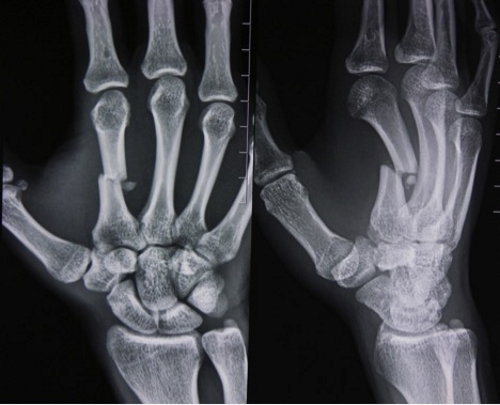

Например, при подозрении на перелом руки травматолог направит пациента на рентген. Эта процедура поможет определить тип и характер перелома, а также наличие смещения или отделения костных осколков. На основе полученных результатов будет назначено соответствующее лечение.

Врачи отмечают, что рентгеновское обследование кисти руки является важным инструментом для диагностики различных заболеваний и травм. С его помощью можно выявить переломы, вывихи, а также изменения, связанные с артритом или остеопорозом. Специалисты подчеркивают, что рентген позволяет получить четкое изображение костной структуры, что особенно важно при оценке состояния суставов и мягких тканей. Однако врачи также предупреждают, что рентген не всегда дает полную картину, и в некоторых случаях может потребоваться дополнительное обследование, например, МРТ или УЗИ. В целом, рентген кисти остается одним из самых доступных и эффективных методов диагностики, позволяющим врачам быстро и точно ставить диагнозы и назначать соответствующее лечение.

Если необходимо сделать снимок запястья и кисти, пациенту предлагают расположить руку на кассете ладонью вниз и максимально распрямить пальцы. Рука должна быть зафиксирована так, чтобы кисть находилась на одной линии с локтем. Для получения более детальной информации могут быть выполнены снимки в боковых проекциях.

Для диагностики переломов фаланг пальцев рентгенография проводится аналогично исследованию запястья, обязательно в двух проекциях. Это необходимо для определения наличия смещения кости. Точно так же поступают и при вывихе большого пальца, когда рентген позволяет выяснить, не осложнен ли вывих переломом.

| Прямая проекция кисти | Кости запястья, пястные кости, фаланги пальцев, суставы | Переломы, вывихи, артриты, остеоартроз, кисты, опухоли костей |

| Боковая проекция кисти | Кости запястья, пястные кости, фаланги пальцев, суставы в боковой проекции | Переломы, вывихи, оценка суставного пространства, остеофиты |

| Косая проекция кисти (по показаниям) | Более детальная визуализация отдельных костей запястья | Выявление скрытых переломов, оценка мелких костных фрагментов |